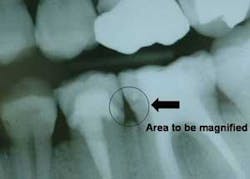

1. Panoramic radiographs. Panoramic radiographs are especially helpful for patient education, because the patient can easily orient the images to their own mouth. Digital panoramic radiographs are much better than analog panoramic radiographs for patient education. You can modify them in many ways (adding contrast, cropping, magnifying) to simplify the patient educational value.

3. Digital radiography. I strongly suggest incorporating digital radiography into your practice as soon as you can afford it (Figures 2 to 5). Although the initial digital images are not better than analog images, they can be enlarged, colored, textured, and have contrast changed, thereby increasing patient education potential and your diagnostic ability.